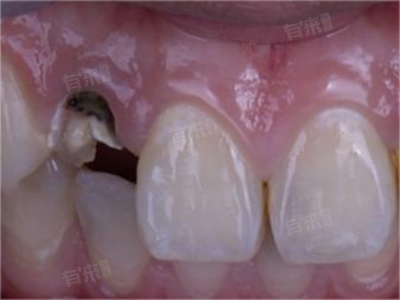

牙齿只剩下残根,通常是由于长期的龋病、牙周病、牙齿外伤或磨损等因素导致。面对这种情况,患者不必过于担心,可以选择根管治疗与桩冠修复、覆盖义齿修复等方法进行处理。

1、根管治疗与桩冠修复:如果牙根情况良好,长度足够且稳固,首选根管治疗,这一方法旨在清除根管内的感染物质,消除炎症,并在根管内打入桩,为后续的牙冠修复提供支撑。完成根管治疗后,可以制作一个牙冠套在桩上,以恢复牙齿的正常功能和美观。

2、覆盖义齿修复:对于牙根较短但仍有一定保留价值的情况,可以考虑覆盖义齿修复,这种方法是在牙根上制作一个基托,并在其上安装义齿,以恢复牙齿的咀嚼功能。覆盖义齿具有制作简单、费用较低的优点。

4、拔除与可摘义齿修复:如果牙根损伤严重,无法保留,那么就需要将其拔除,拔除后,患者可以选择可摘义齿进行修复。可摘义齿通过卡环和基托固定在口腔内,可以自行摘戴,方便清洁和维护。

5、种植牙修复:种植牙是一种先进的口腔修复技术,通过在牙槽骨内植入人工种植体,待种植体与牙槽骨结合后,再安装牙冠。这种方法能够恢复牙齿的功能和美观,且效果持久稳定,种植牙适用于牙根无法保留、且患者希望获得更持久修复效果的情况。